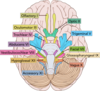

Pathophysiology of acute pancreatitis

Pancreatic enzymes released and activated-> multi stage process

Oedema + fluid shift + vomiting —> hypovolaemic shock

Enzymes—-> autodigestion

Vessel autodigestion—> retroperitoneal haemorrhage

Inflammation—–> pancreatic necrosis

Implications of pancreatic necrosis

Super-added infection in 50% of patients with necrosis